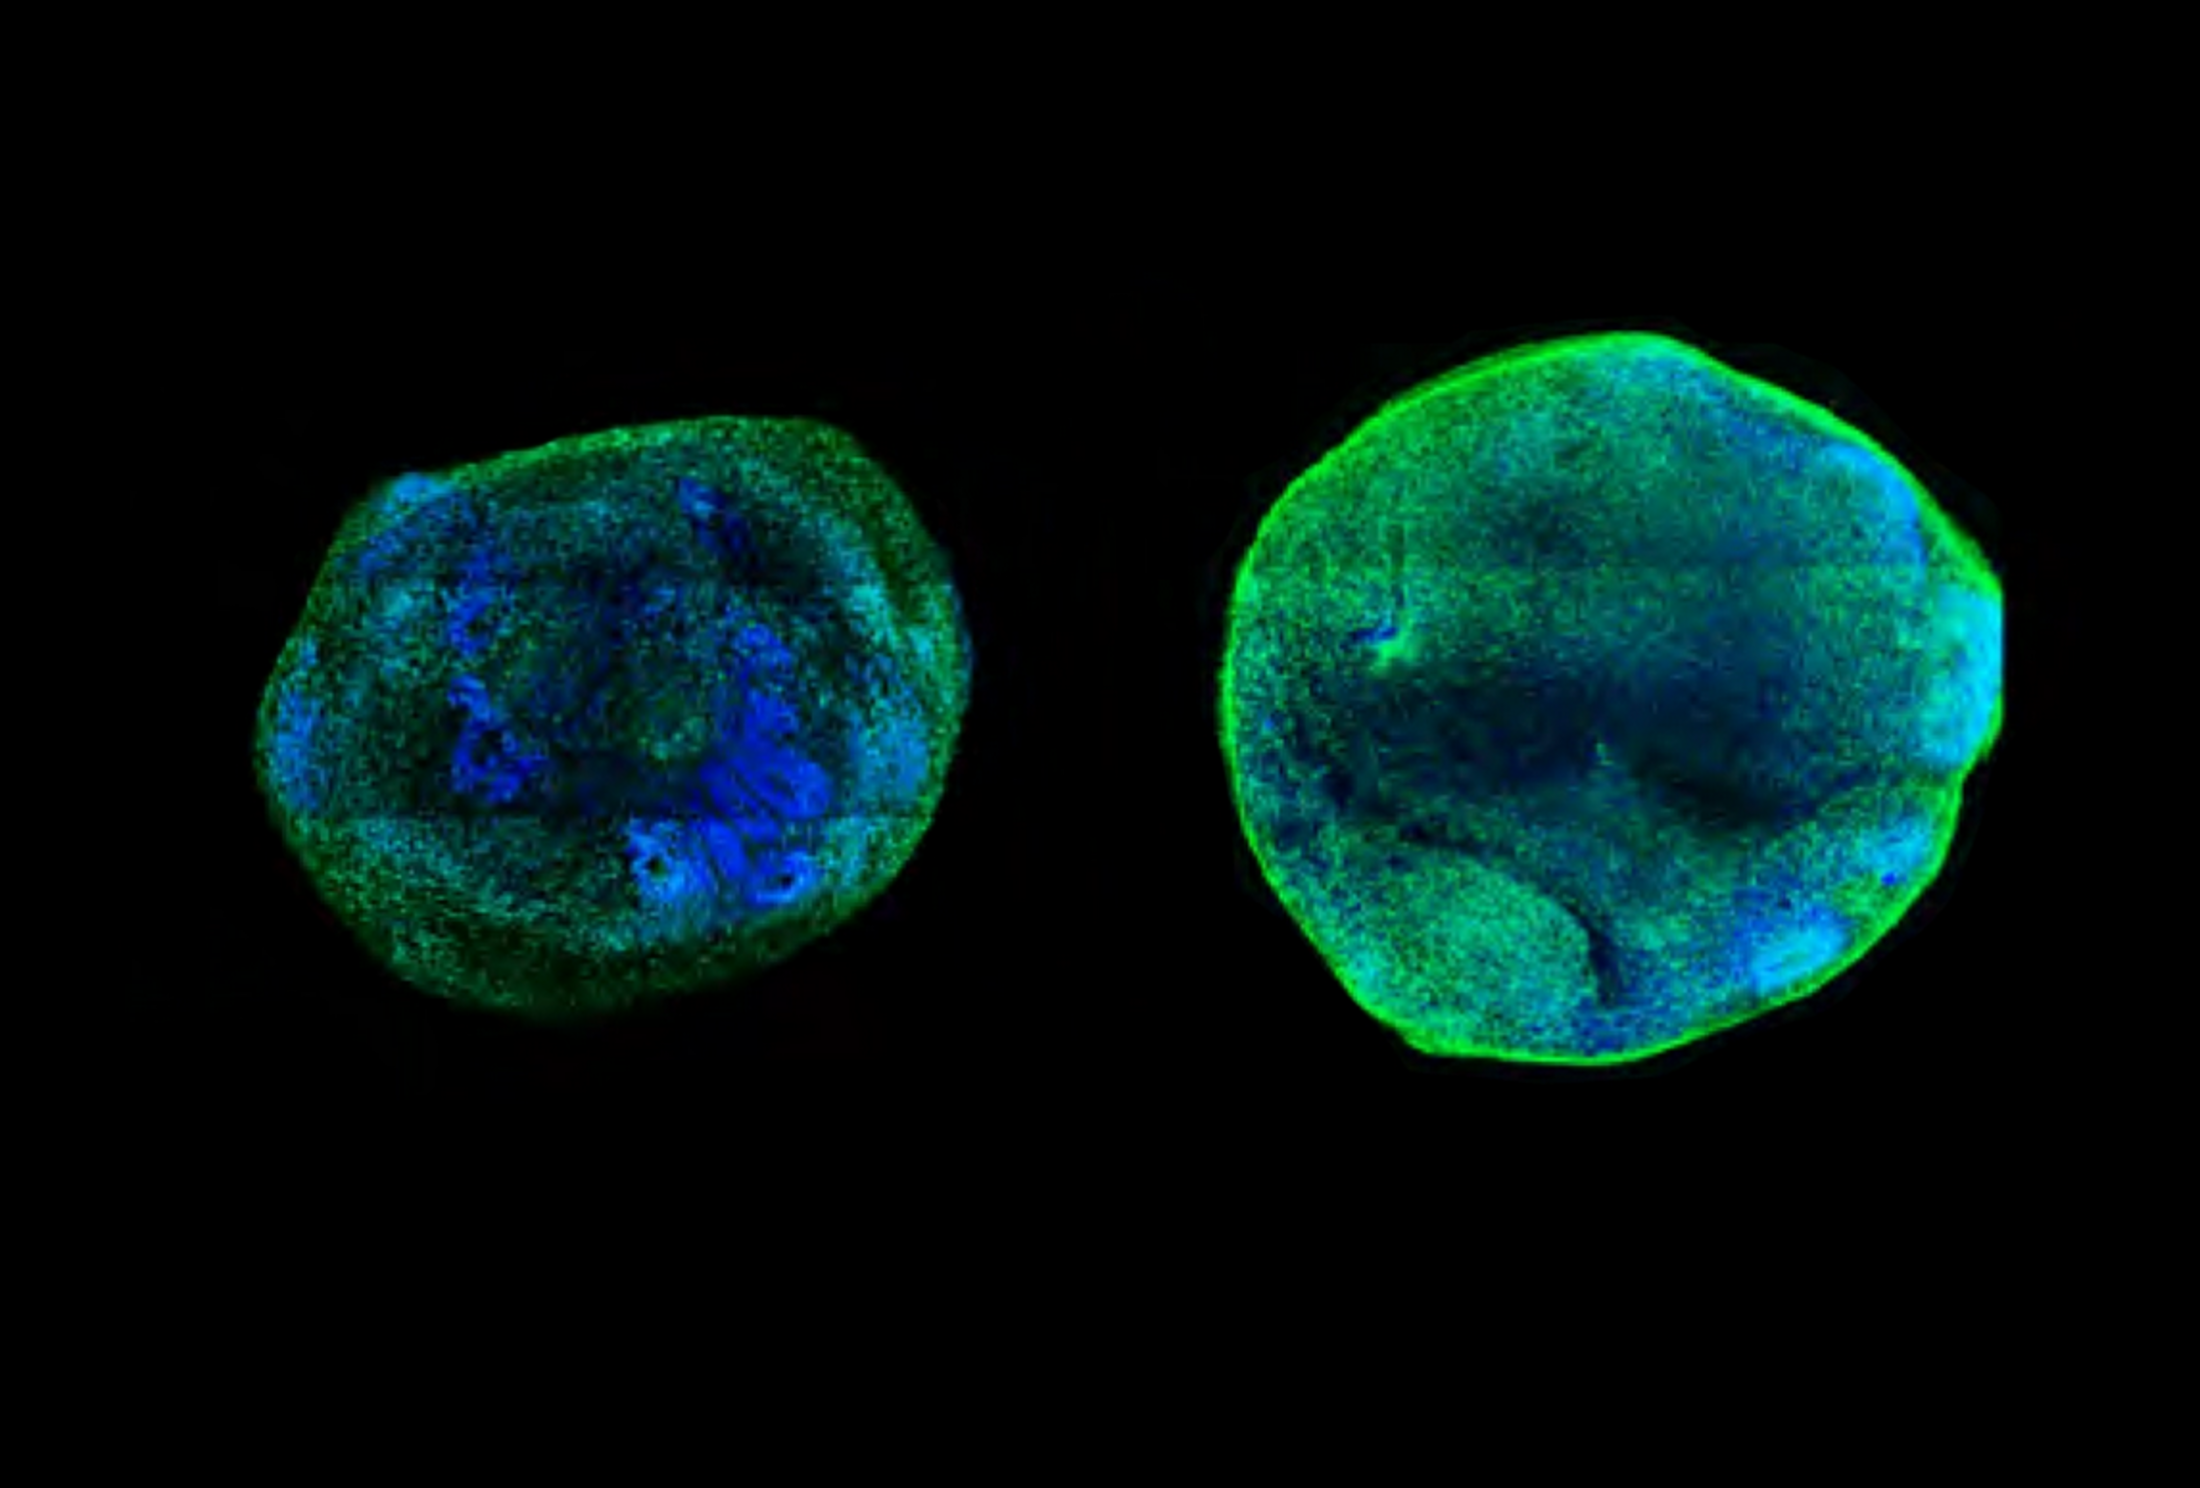

Illustration 1

Absence : La coloration fluorescente d'organoïdes modifiés pour n'avoir qu'une seule copie fonctionnelle de CHD8 (à gauche) ou de SCN2A (à droite) montre une diminution des niveaux des protéines généralement produites par ces gènes.

La stimulation des enhancers de CHD8 dans les neurones et les organoïdes cérébraux dépourvus d'une copie fonctionnelle de ce gène a entraîné une réduction de la taille de l'organoïde et du nombre de gènes exprimés de manière différentielle. Cette découverte suggère que l'intervention peut sauver des cellules : sans elle, les organoïdes mutants CHD8 sont plus grands et présentent une surprolifération de cellules progénitrices neurales par rapport aux témoins qui ont deux copies fonctionnelles du gène.